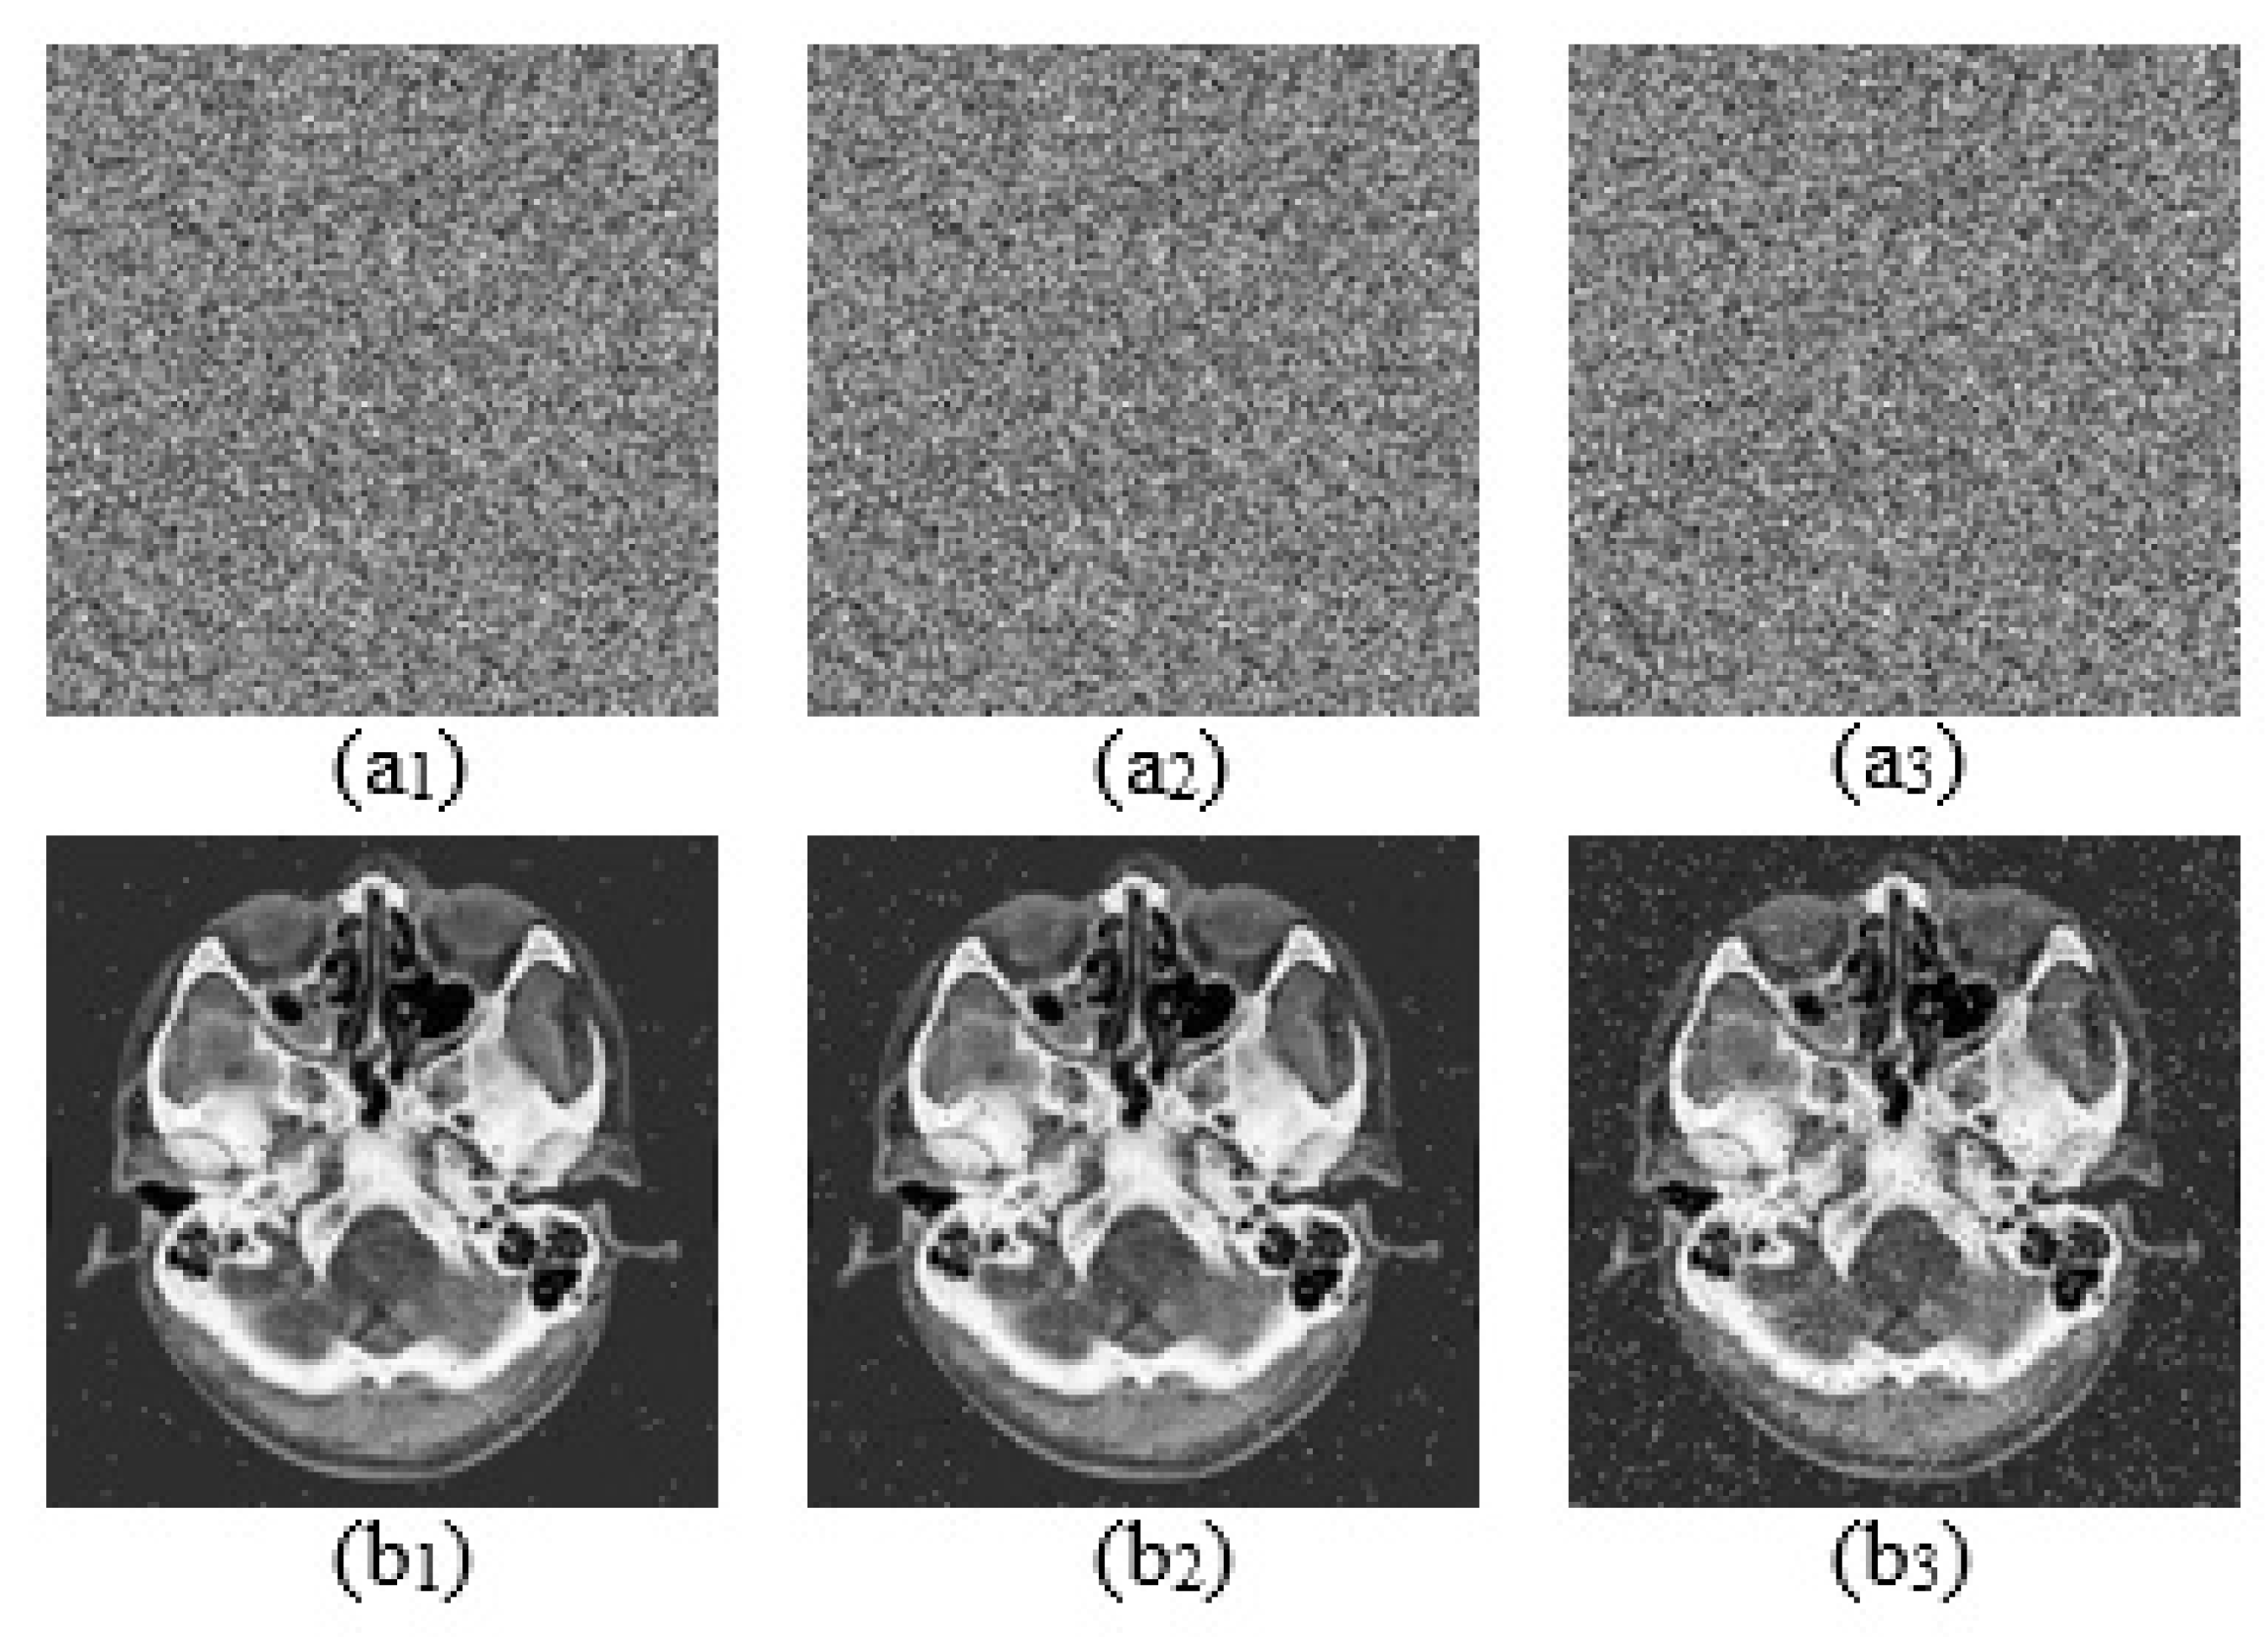

Key sensitivity analysis

The aim here is to test the algorithm’s performance against extremely slight changes in parameter values. This analysis is carried out by introducing a slight perturbation of the order of 10 15 in the values of the parameters and initial conditions. The results of this analysis are shown in Figure 26.

The results in Figure 26 show that when a slight perturbation is introduced in the values of the parameters and initial conditions, it is no longer possible to obtain the original image. This confirms that the algorithm is extremely sensitive to slight variations in the key.

Figure 26. Key sensitivity test results. (a) Correct keys, (b) a + 10 15 , (c) b + 10 15 , (d) c + 10 15 , (e) d + 10 15 , (f) e + 10 15 , (g) x 0 + 10 15 , (h) y 0 + 10 15 , (i) z 0 + 10 15 .